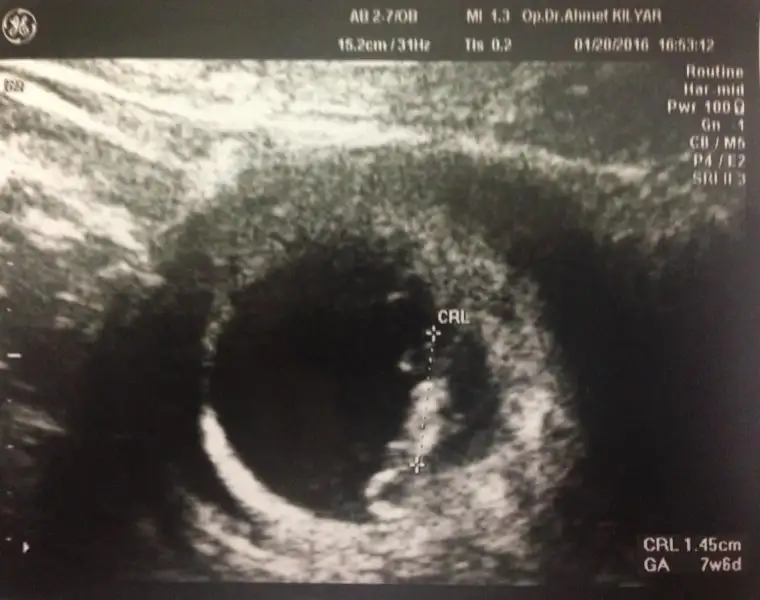

Plasenta solda görünüyor gerçekte sağda demktir bu erkek olma ihtimali yüksek olduğunu gösterir.Cnm bunun plesantasi nerde cinsiuet ne olabilir karindan bakilma 6 haftalik

Plasenta solda görünüyor gerçekte sağda demktir bu erkek olma ihtimali yüksek olduğunu gösterir.